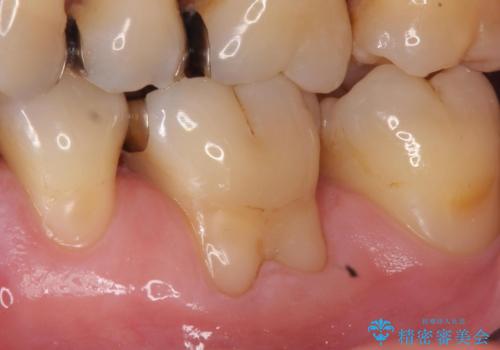

- 奥歯の歯茎が下がっていて(歯肉退縮)歯が染みるとのことで来院された患者様です。

退縮した歯茎に対して移植をすることで、しみる場所を覆う計画です。

歯根の分岐部よりも根尖側の頬側面が露出している状態でしたが、露出部位を分岐部までに抑えることができました。